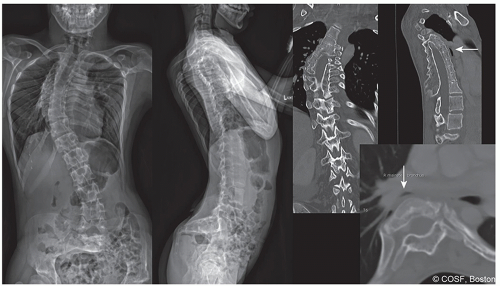

The secondary effects of the spinal deformity may be of greater or equal significance than the spine curvature itself (Figure 1.3). The interrelationship between the evolution of thoracic early onset scoliosis (EOS) and chest wall deformity leading to thoracic insufficiency syndrome (TIS) is an excellent example where the long-term effect on chest wall shape, lung development, and mechanics of thoracic function are often more problematic than the spine curve itself (Figure 1.4). Avoidance of TIS, a secondary effect, often drives surgical decision-making in EOS. Localized congenital or other curves may have a profound negative effect on the adjacent, previously normal spine (Figure 1.5). An abrupt upper lumbar congenital kyphosis or the thoracolumbar kyphosis associated with bone dysplasias or storage disorders may with time produce permanent thoracic lordosis above or painful hyperlordosis below. Persistent severe pelvic obliquity from lumbar scoliosis in the young child may effectively uncover one hip, contributing to hip dysplasia (Figure 1.6). Persistent pelvic obliquity in the nonambulatory neuromuscular patient reinforces the trend toward hip subluxation and adduction contracture. Surgical decision-making needs therefore to take into account the possible permanent effect of the evolving deformity on the rest of the spine and adjacent structures, not just the spine alone.